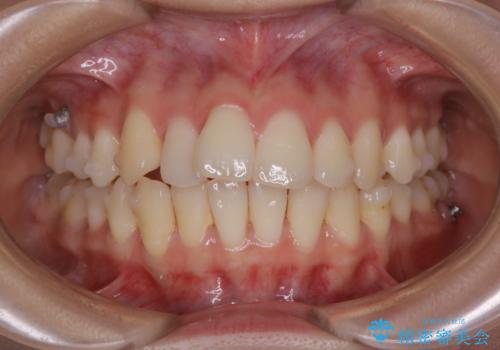

マイクロインプラントとIPR

歯を並べるスペースを作るために、歯の遠心移動と歯列の拡大、歯自体を少しだけ小さく削る(IPR)という方法を複合的に組み合わせて配列を行いました。遠心移動用のゴムかけにはマイクロインプラントという小さいネジを用いて骨に直接固定源を求めました。